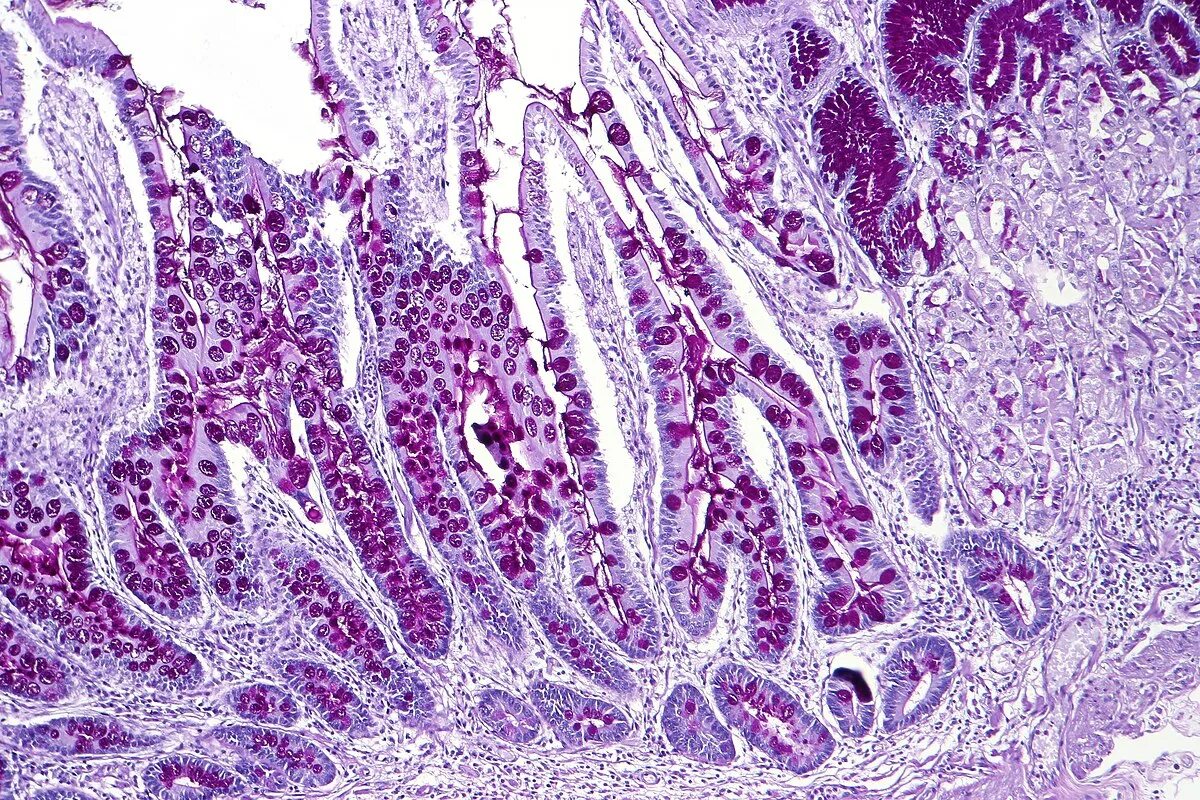

Отдел гистологии